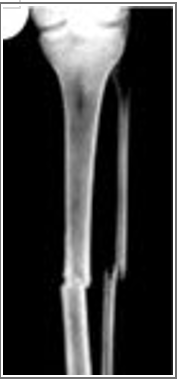

Match the correct description of the X-ray fracture to the image.

Fracture caused by direct impact to the leg.